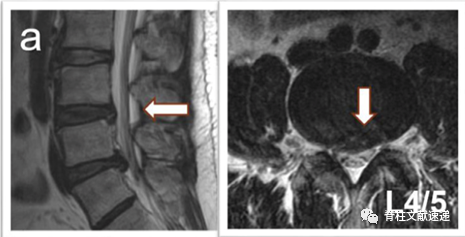

病例一:L5/S1椎间盘突出症,L4/5无症状椎间盘突出,行L5/S1固定融合术,3年后出现L4/5椎间盘突出症,行手术治疗,如下图,a为术前,b为术后。